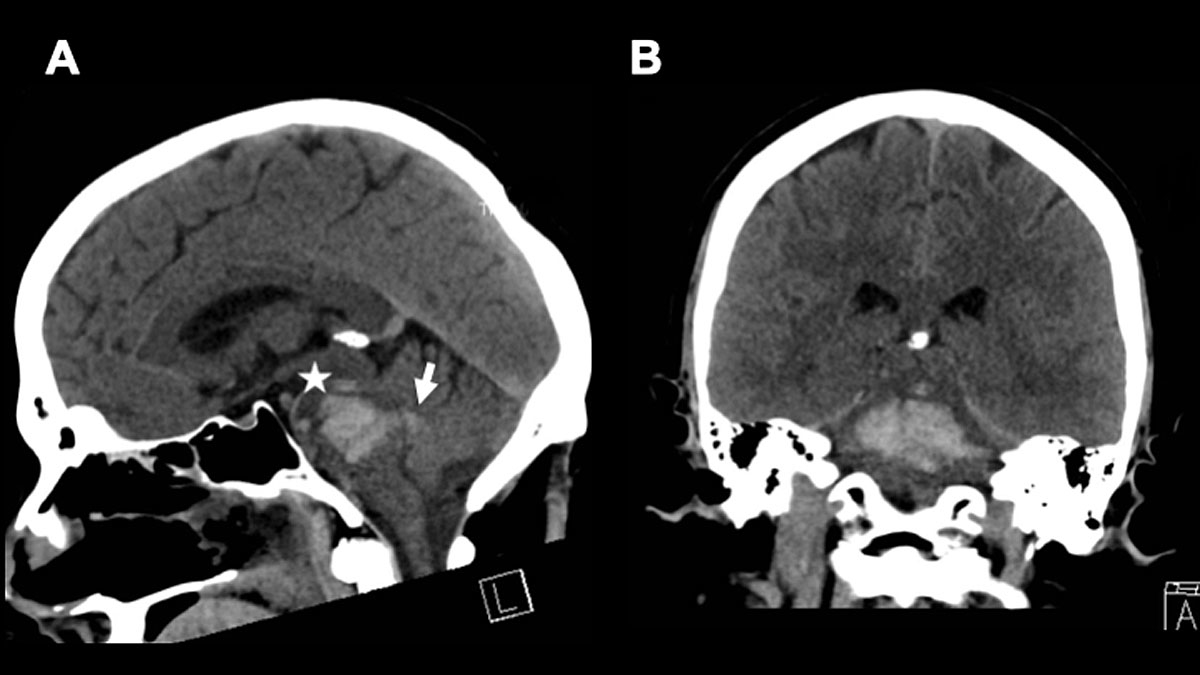

The role of electroencephalogram (EEG) in brainstem monitoring remains highly disputed. It has been shown that the stimulation of the brainstem (e.g. the reticular formation) evokes changes in the EEG [30]. However, performing an EEG as part of brainstem monitoring, and especially in brainstem death diagnostics, is claimed to be more reassuring for the patients’ relatives than practical enough to guide clinical decision-making, for the obvious reason that recording an EEG from the scalp can hardly test brainstem function [31] (fig. 4 presents an illustrative case).

Figure 4 A 47-year-old male patient presented with an initial GSC of 3 at hospital admission. CT diagnostics revealed a “massive” brainstem haemorrhage. Electrophysiology showed highly pathological results (SEP, AEP and EEG). The patient was extubated on day +4 under a palliative care concept. A. shows a sagittal view and B. an axial view of the initial CT scan. * indicates the haemorrhage and → indicates the ventricular extension of the haemorrhage. Ventricular extension may cause hydrocephalus.